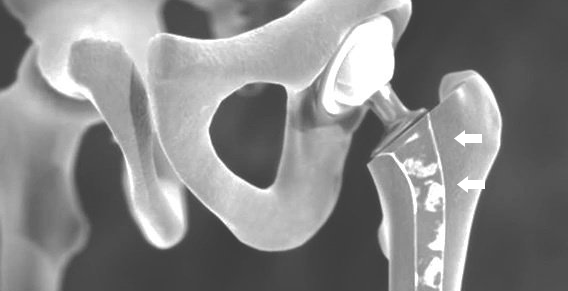

فيما يتعلق بمفصل الورك، وخاصةً عدوى المادة الاصطناعية، فإن الإنهاء المبكر للعمود أو كسر العظم الذي ينطوي على الغرسات يخشى حدوث مضاعفات.

يمكن إعادة تشغيل OFT باستخدام غرسة الورك الأولية عند استبدال الطرف الاصطناعي. في بعض الأحيان تكون عمليات زرع المراجعة الخاصة ضرورية أيضًا.